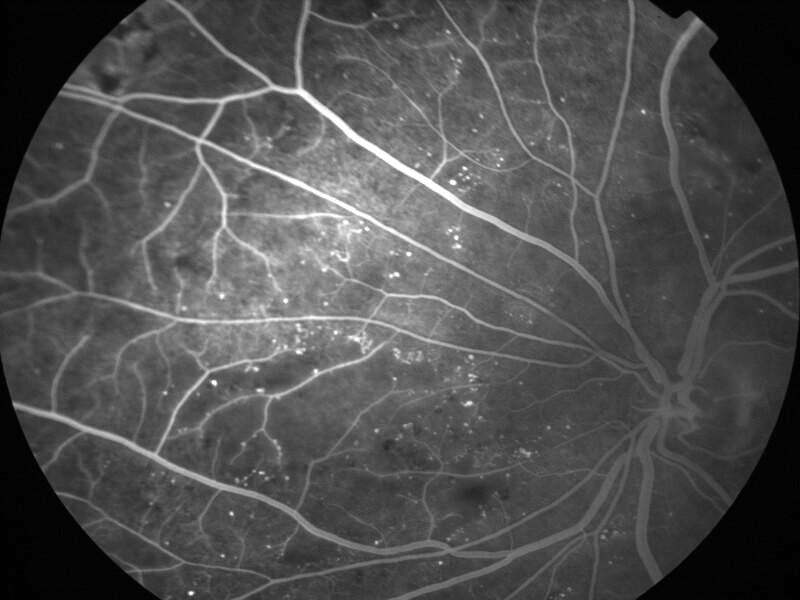

rétinopathie diabétique pré-proliférante

IM000001.jpg